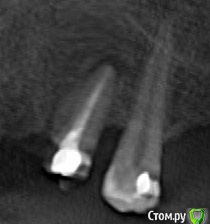

alex_ddd Опубликовано 27 июля, 2016 Автор Поделиться Опубликовано 27 июля, 2016 Да, пятерку врачи оценивали скептически, тем не менее ее перелечили, в гранулему ввели лекарство какое-то, теперь в зубе вкладка и на ней коронка временная. Как же мне им заняться? Наверное просто ждать..Вот снимок до лечения (кроп из скриншота панорамного) : а имплантат мне хирург выкрутил сегодня обратно. такие дела Ссылка на комментарий

___49___ Опубликовано 28 июля, 2016 Поделиться Опубликовано 28 июля, 2016 (изменено) Если на втором снимке состояние 5 ки после "лечения".... соглашусь с stomm , зуб с большей долей вероятности на удаления. Скажем так - процент удачного излечения переодонтита (такой диагноз был у вашей 5 ки до лечения) от 60 %.....в вашем случае лечение не задалось удалось. Изменено 28 июля, 2016 пользователем ___49___ Ссылка на комментарий

stommm Опубликовано 28 июля, 2016 Поделиться Опубликовано 28 июля, 2016 Если судить только по представленным снимкам, то до выглядит лучше чем после.Наверное с вкладкой 4-й зуб, а имплант был на месте клыка? Судя по фрагменту панорамы. Как 2-ка себя ведет? Боль прошла? Ссылка на комментарий